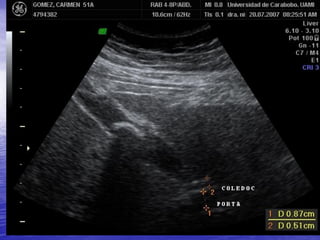

VIA BILIAR EXTRAHEPATICA

• ANATOMIA NORMAL

El segmento mas visible es el conducto

hepático común que tiene una situación

anatómica constante y puede detectarse

fácilmente en el sistema portal, cruzando

anterior a la vena porta derecho no

dividida y forma el conducto biliar común

• TAMAÑO DEL CONDUCTO BILIAR

EXTRAHEPATICO

La literatura describe desde 4 hasta 8 mm y

10 mm en ancianos como limite alto normal

Otra regla de medición:

40 años: 4mm

50 años: 5mm

60 años: 6mm

Se acepta un diámetro menor en porción

proximal que en distal adoptando forma de

embudo lo cual puede ser imperceptible o

dilatación evidente lo que traduce obstrucción

precoz del conducto biliar extrahepatico